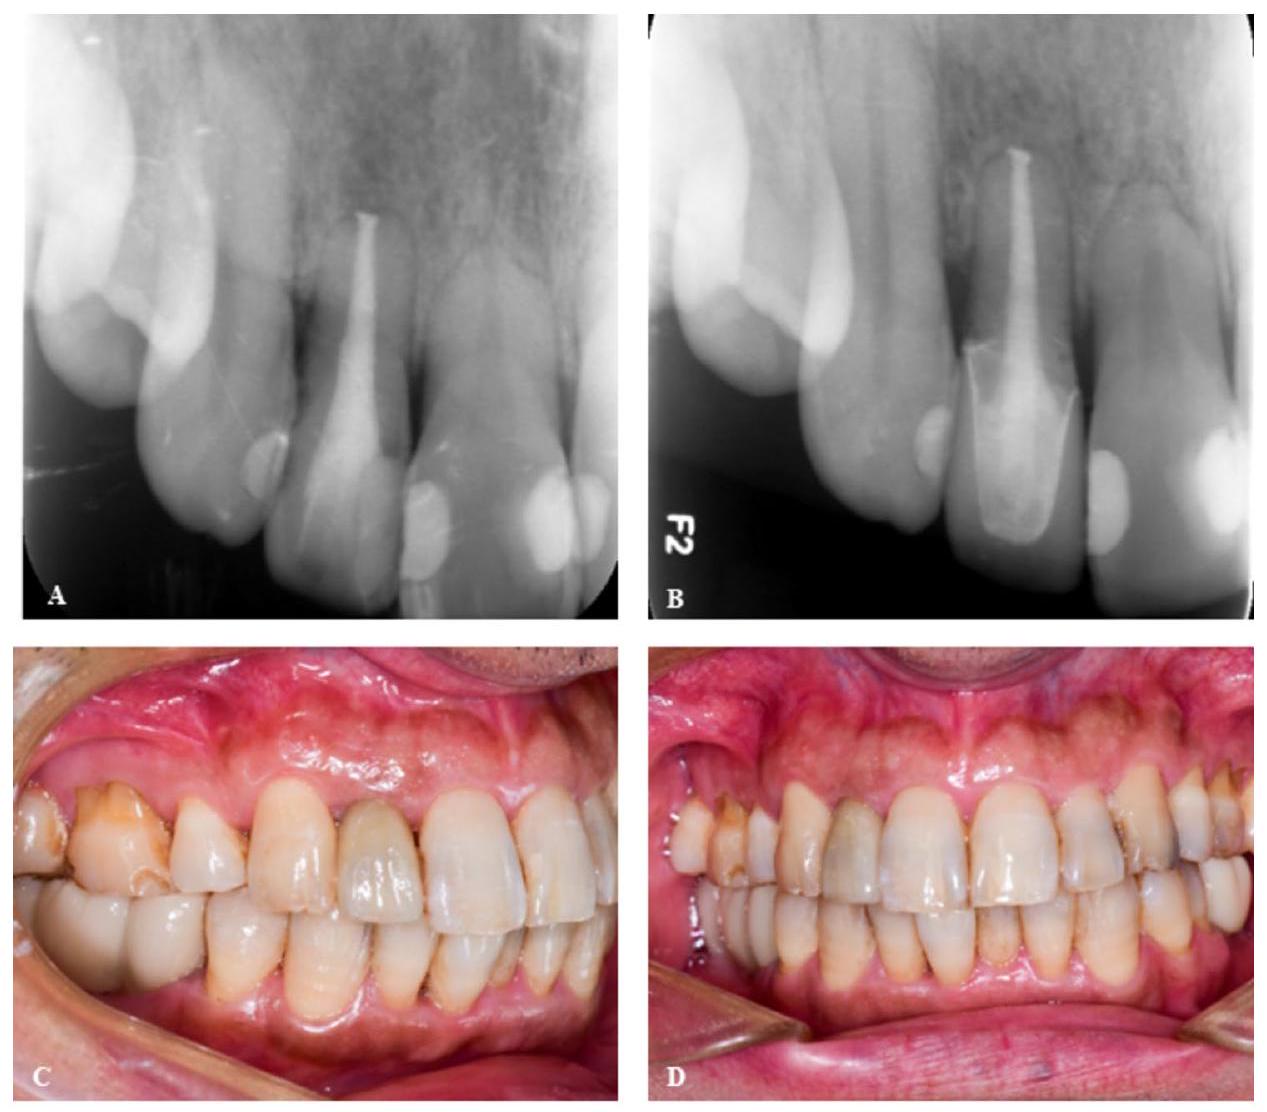

three-dimensional reconstruction and alignment, incorporating the imported DICOM and STL data. In this case, the clinician marked the long axes of the maxillary right lateral incisor using the software. The design of the operation plans included determining the fractured file took-out method, size and shape of the bone window, and appropriate drill. Despite the short root of the affected tooth and absorption of the distal alveolar bone, the tooth exhibited a large circumference, which was asymptomatic and stable. No infections were observed in the periapical tissues of the teeth. Therefore, preservation of the affected tooth without root resection was an appropriate course of action during surgery. Because the length of the fractured file was approximately 7 mm , to

ensure a minimally invasive bone window shape, it was removed in two stages. After measurement and calculation using the software, we found that the diameter of the round-shaped bone window prepared by the ATR system was 3 mm , directly exposing the upper segment of the fractured file and the apex ( 0.5 mm ) (Fig. 2). Then, the round bone window was prepared, free handedly, under a microscope to form a 1.5 mm slender isthmus, and finally a keyhole-shaped bone window. The longest measured bone window was approximately 4.5 mm . After the upper segment of the fractured file was cut off the bone window, the lower part of the 4.5 mm -length fractured file remnant was removed through the 4.5 mm -length bone window using microscopic forceps. Because of the small diameter of the bone window, a small ball drill ( 3 mm ) was required to precisely locate the fractured file. Personalized surgical accessories (Fig. S1.) were manufactured using 3D printing (Pro S95; SprintRay Co., Los Angeles, CA, USA) before surgery. The operator practiced using the robot in advance to verify if the operation plan was reasonable (including the position and depth of the

A 3 mm -ranged bone cavity was prepared directly on the fractured file as per the preoperative plan. Because the fractured file length was 7 mm , the surgeon further

prepared the cavity to a 4.5 mm -length key-like shape to facilitate the removal of the fractured file in two segments (Fig. 3E). The 4.5 mm -length lower segment of the fractured file was sufficient to exit the keyhole-shaped bone window (Fig. 3F-G). The root tip was inspected to confirm that the well was enclosed by the iRoot BP Plus. The flaps were closed with monofilament sutures. While the preparatory work was lengthy (approximately 30 min ), the ATR system opened the bone window and allowed for operator pick up of fractured file in only 9 min .